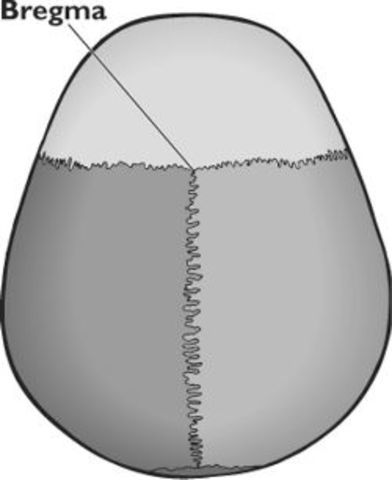

• Tres meses

Tres meses

Cierre de la sutura anterior o Bregma

• Cierre de las suturas craneales y la fontanela posterior

Cierre de las suturas craneales y la fontanela posterior